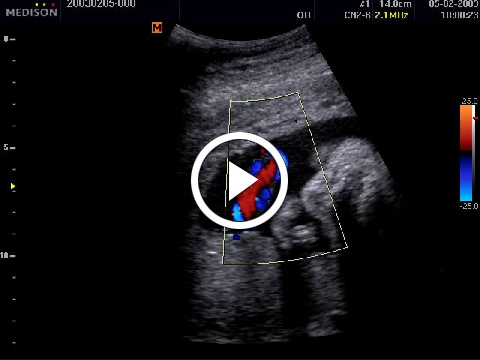

Color Doppler mód

(Színes Doppler mód)

A Color Doppler mód vagy duplex vizsgálat az erekben áramló vér áramlásának megjelenítésére szolgáló képalkotás. Az ultrahang készülékek ehhez a Doppler-effektust alkalmazzák a transducer irányába tartó, vagy attól távolodó áramlások irányának és sebességének meghatározására, és színkódolt megjelenítésére a monitoron. A Color ablakon belül eltárolják a következő információkat: áramlás iránya, áramlási sebesség, és ezeket az információkat színekké kódolva visszaírják a B-képbe.

Egy szülészeti példa a köldökzsinór ereinek vizsgálata: